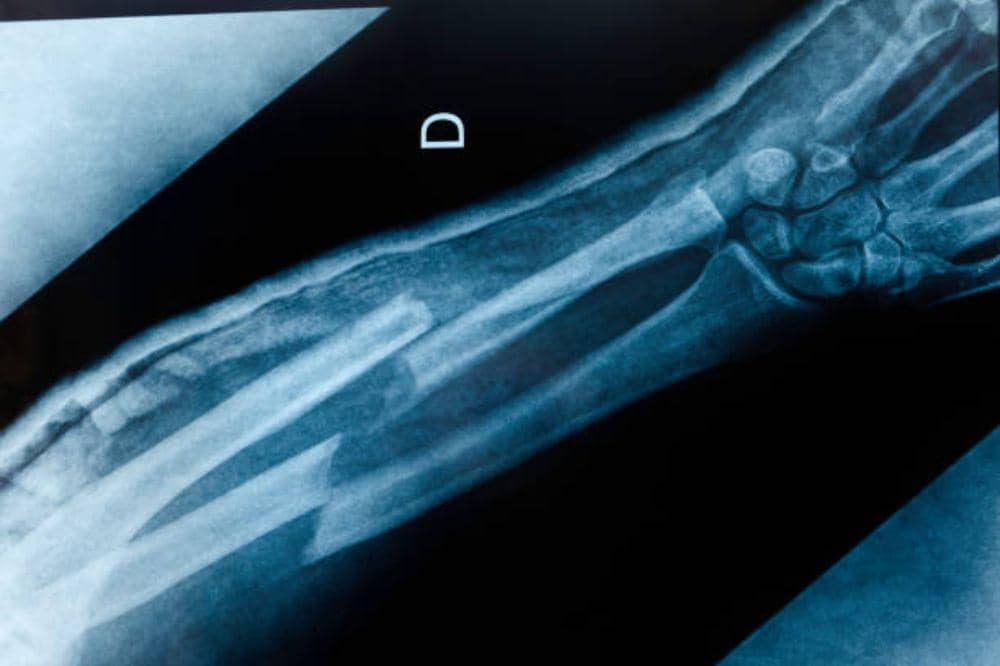

4. Tulang mudah retak atau patah

Jika tulang mudah retak atau patah hanya karena jatuh ringan atau benturan kecil, kondisi ini patut diwaspadai. Pada orang dengan tulang sehat, benturan ringan biasanya tidak langsung menyebabkan patah tulang.

Namun, pada penderita osteoporosis, tulang menjadi sangat rapuh. Akibatnya, cedera kecil bisa berujung fraktur. Menurut penjelasan medis, osteoporosis membuat struktur tulang menjadi keropos dan kehilangan kekuatan.

Lokasi patah yang sering terjadi adalah pergelangan tangan, tulang pinggul, dan tulang belakang. Proses pemulihan pun cenderung lebih lama. Kondisi ini tentu berdampak besar pada kemandirian Mama dan Papa.